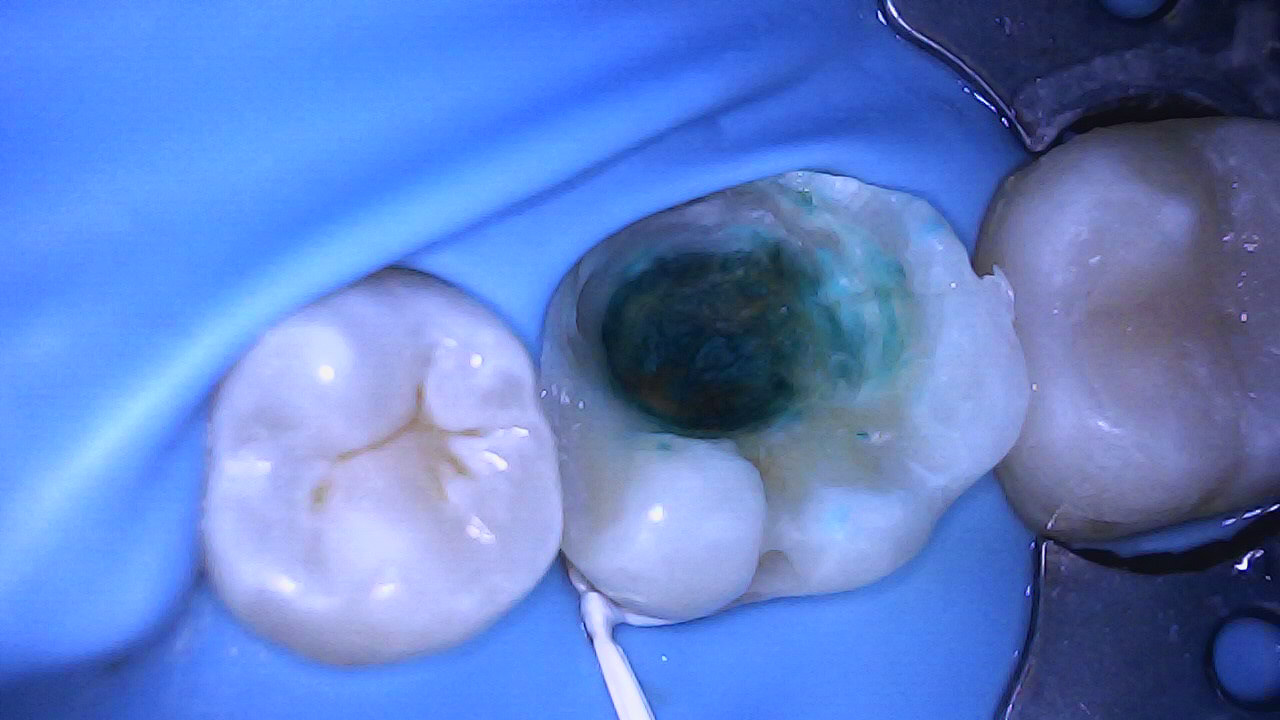

Selective caries removal with help from caries dye